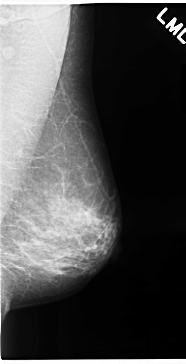

C_0115_1.LEFT_MLO

LEFT_MLO LINES 4720 PIXELS_PER_LINE 2408 BITS_PER_PIXEL 12 RESOLUTION 50 NON_OVERLAY